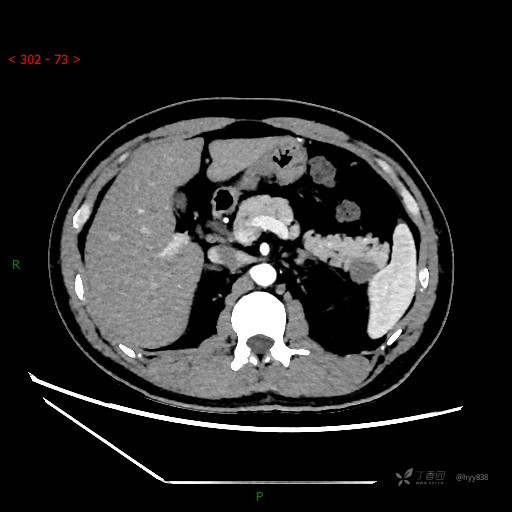

增强动脉期

CT值

42hu 48hu 57hu